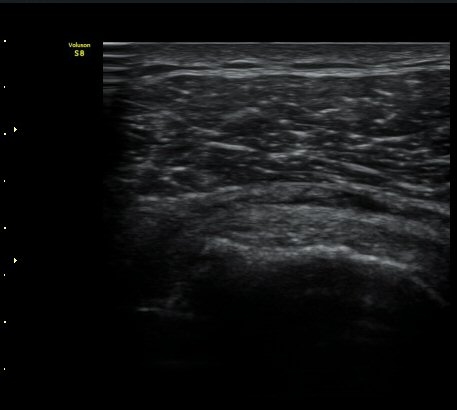

ÃÊÀ½ÆÄ °Ë»ç

±Ø»ó°Ç Á¾´Ü¸é°Ë»ç½Ã ±Ø»ó°Ç ºÎÂøºÎ¿¡ Àú¿¡ÄÚ ºÎÁ¾°ú ¹Ì¼¼ÇÑ °Ç ¿¬°á¼º ¼Ò½ÇÀÌ

°üÂûµÊ (±×¸² 1, 2, 3 )